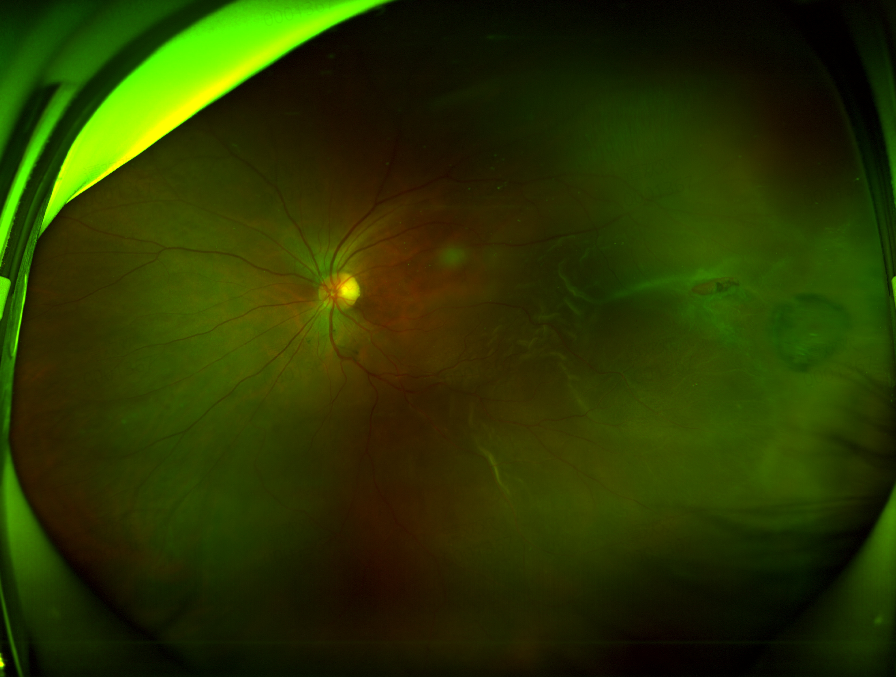

62岁的Z女士(化名)因左眼黑影遮挡感3天入院,检查左眼眼压13mmHg,左眼眼底视网膜颞侧及下方呈灰白色隆起,3点方位有一裂孔视盘边界清,浅红色,C/D约0.3,脱离累及黄斑部,中心反光未见。